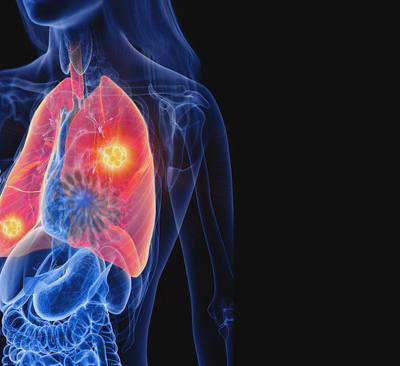

폐렴 증상 폐렴은 폐의 세균, 바이러스, 곰팡이 등 감염으로 인해

폐포(폐 속의 공기 주머니)에 염증이 생기고, 고름이나 액체가 차는 질환입니다.

3. 호흡곤란

- 폐에 염증이 생겨 산소 교환이 제대로 안 되면 숨이 차고 호흡이 가빠짐